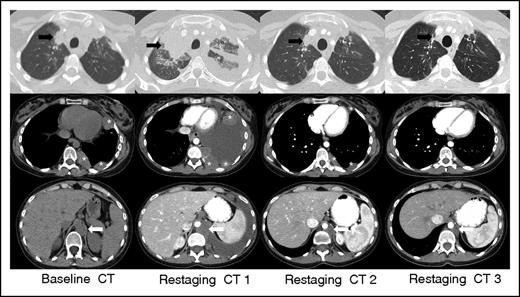

IR(1): Restaging CT 1 at 3 weeks demonstrates overall progression of tumor burden (SPD +124% from baseline) as evidenced interval increase in a right upper lobe lung mass (black arrow), left-sided pleural masses (asterisks), and left retrocrural lymphadenopathy (white arrow), and interval development of a large left-sided pleural effusion. Subsequent follow-up at 7 weeks (restaging CT 2) shows an interval decrease in size of all lesions with resolution of the left pleural effusion (SPD −27% from baseline). Additional follow-up at 13 weeks (restaging CT 3) demonstrates a further interval decrease in tumor burden, and the patient achieved a PR by revised response criteria (SPD −54% from baseline) with clear subsequent clinical benefit from continued treatment.